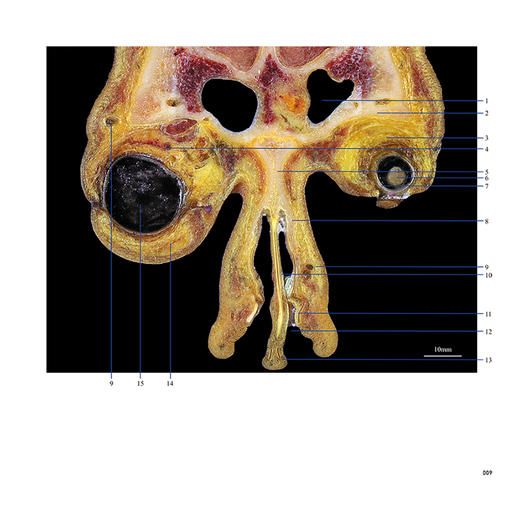

本书从数据集每隔1.2mm选取一幅图像,截取眼、耳、鼻及毗邻颅底的局部区域图像,共112幅图像。同时配以相应部位的CT图像对照。本书特色是断层解剖图利用数字图像处理技术优势,放大并清晰展示眼、耳、鼻及毗邻颅底断面的局部区域结构,组织色泽真实,甚至能够清晰显示肌肉纹理、筋膜纹路等细节结构,图像质量高于美国《人体断层解剖学彩色图谱》(引进版)类似图谱图像质量。对眼科、耳鼻咽喉科和神经内外科医生理解相关解剖结构有较大帮助。